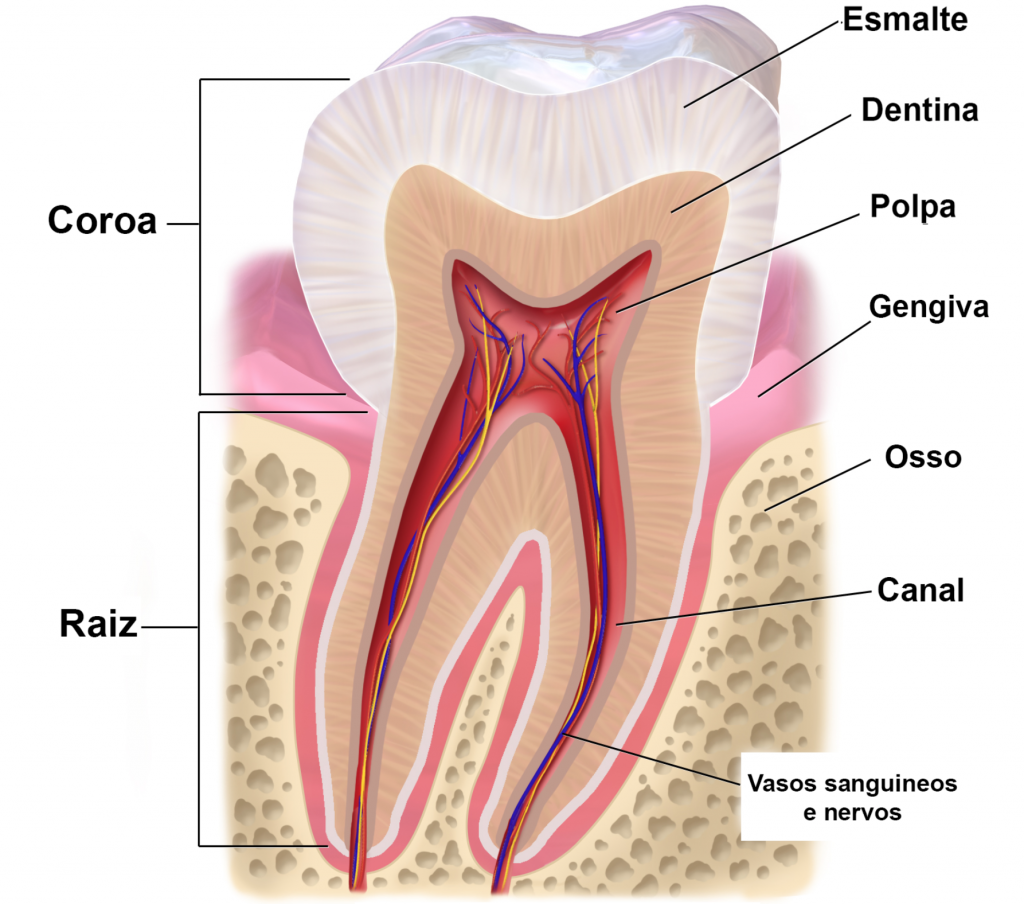

Você quer ver como é o procedimento? A gente te mostra! O tratamento endodôntico, popularmente conhecido como canal, é um processo detalhado para salvar um dente que sofreu danos severos na polpa, aquela parte interna onde ficam os nervos e vasos sanguíneos.

O Coração do Dente: A polpa dental é o tecido mole no interior do dente, que abriga nervos e vasos sanguíneos. Quando ela é afetada por cáries profundas, traumas ou infecções, o tratamento endodôntico se torna necessário para remover essa parte comprometida.

Selando o Futuro: Após a limpeza, os canais são preenchidos com um material obturador, como a guta-percha. Esse selamento impede que bactérias voltem a invadir o espaço, garantindo a longevidade do dente. É como fechar a porta para futuras infecções.

Restauração para Durar: Para finalizar, o dente é restaurado. Dependendo da extensão do dano, pode ser uma restauração simples ou uma coroa mais robusta. O objetivo é devolver a funcionalidade e a estética, permitindo que você volte a sorrir sem preocupações.